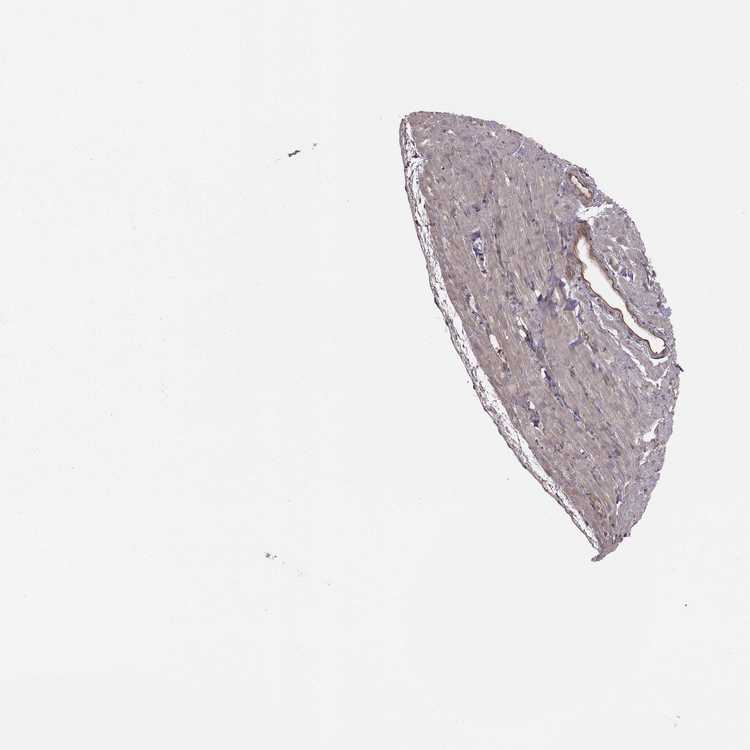

HEART MUSCLE - Antibody stainingi

Antibody staining in the annotated cell types in the current human tissue is reported as not detected, low, medium, or high, based on conventional immunohistochemistry profiling in selected tissues. This score is based on the combination of the staining intensity and fraction of stained cells.

Each image is clickable and will lead to virtual microscopy that enables deeper exploration of all samples and also displays staining intensity scores, fraction scores and subcellular localization as well as patient and tissue information for each sample.

Antibody HPA069341Antibody CAB007781

Cardiomyocytes Not detectedNot detected